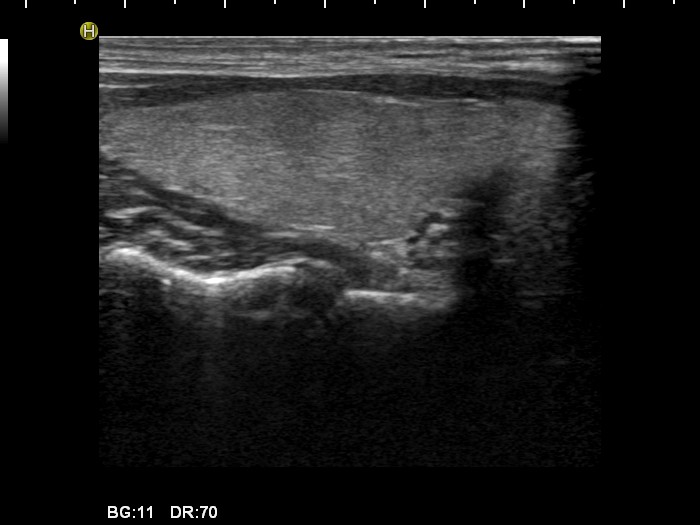

100 consecutive cases of papillary cancer - case 037 (ultrasonographic picture 2)

Right lobe, longitudinal view.